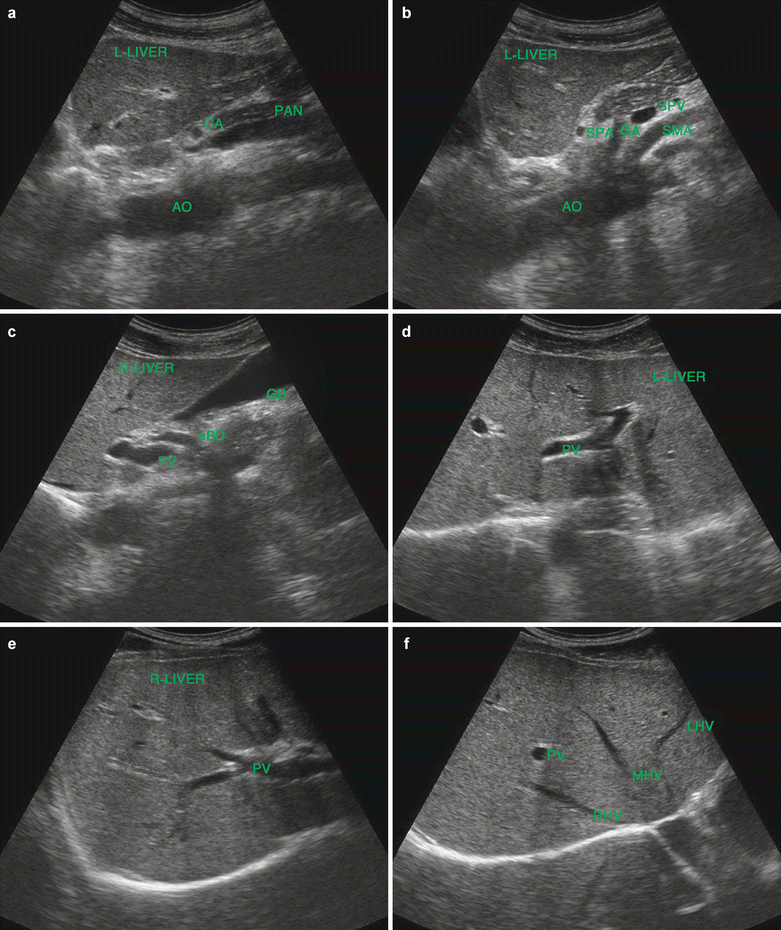

From radiologykey.com

Conventional ultrasound findings in chronic liver disease Radiology Key Autoimmune Hepatitis Liver Ultrasound Autoimmune hepatitis is a chronic, inflammatory disease of the liver that is characterized by circulating autoantibodies and. If you have autoimmune hepatitis, you will have more liver enzymes in your blood. If your liver blood tests. Autoimmune hepatitis is an inflammatory disease of the liver of unknown cause that may progress to liver cirrhosis and end stage liver failure if. Autoimmune Hepatitis Liver Ultrasound.